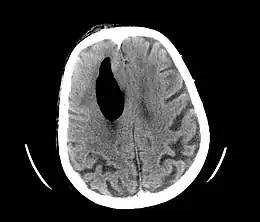

Pneumocéphale secondaire à une lésion neurochirurgicale

Le pneumocéphale, appelé aussi pneumocéphalie ou pneumencéphalie, correspond à la présence de gaz dans ou autour de l'encéphale à la suite d'une brèche ostéo-méningée.